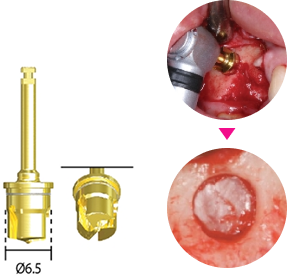

Имплантовод

| Артикул | Фото | Длина |

| ISFD10R |  |

Короткий |

| ISFD15R |  |

Длинный |

| ISFD05C |  |

Под угловой наконечник |